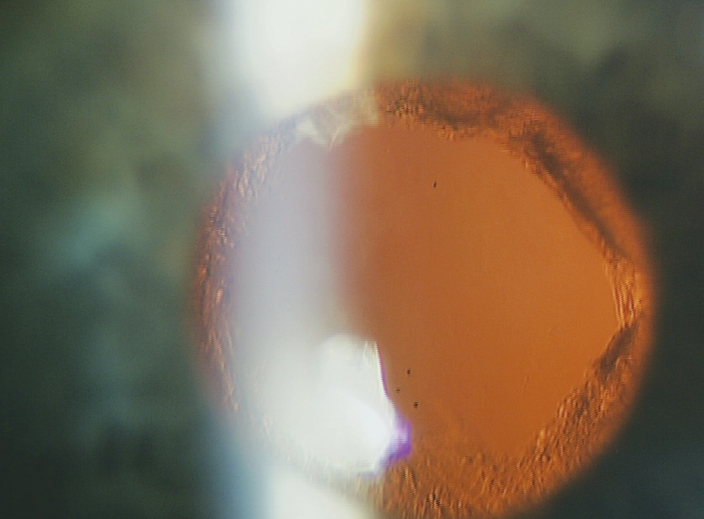

Через 7 месяцев ношения минисклеральных линз пациент предъявил жалобы на ухудшение зрения левого глаза. При визометрии острота зрения левого глаза в линзе составила 0,13. При биомикроскопии выявлен фиброз задней капсулы. Была запланирована Nd:YAG-лазерная дисцизия вторичной катаракты. В назначенный день процедуру пришлось отменить из-за невозможности фокусировки прицельного луча на задней капсуле в связи с выраженным роговичным астигматизмом. Вскоре решение данной проблемы было найдено — выполнение Nd:YAG-лазерной дисцизии при надетой минисклеральной линзе. Через надетую ЖГМСКЛ удалось точно сфокусировать прицельный луч на задней капсуле и произвести Nd:YAG-лазерную дисцизию вторичной катаракты (рис. 2). Параметры воздействия: энергия импульса в пределах — 0,9–1,2 мДж; количество импульсов — 18, топография нанесения импульсов по методике «вскрытия консервной банки». После процедуры острота зрения левого глаза в минисклеральной линзе составила 0,5. Пациент продолжил успешно носить линзы и наблюдаться в клинике. В течение всего срока наблюдения (14 месяцев) воспалительные заболевания и осложнения, связанные с ношением линз, отсутствовали. Кроме того, долговременное ношение минисклеральных линз не вызвало патологических гипоксических изменений морфологической структуры эндотелия роговицы (см. табл. 3).

Рис. 2. Биомикроскопическая картина результата выполненной Nd:YAG-лазерной дисцизии вторичной катаракты

Fig. 2. Biomicroscopy image showing the result of Nd:YAG laser posterior capsulotomy